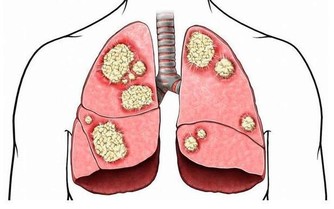

頭痛是過度水合和脫水的跡象,類似於噁心、嘔吐和腹瀉。當你喝太多水時,血液中的鹽濃度會降低,導致全身器官中的細胞膨脹。當你的體內鹽濃度很低時,細胞就會生長。當你喝太多水時,大腦實際上會變大並壓在頭骨上。這種增加的壓力會導致跳動性頭痛和更嚴重的健康問題,如腦損傷和呼吸困難。